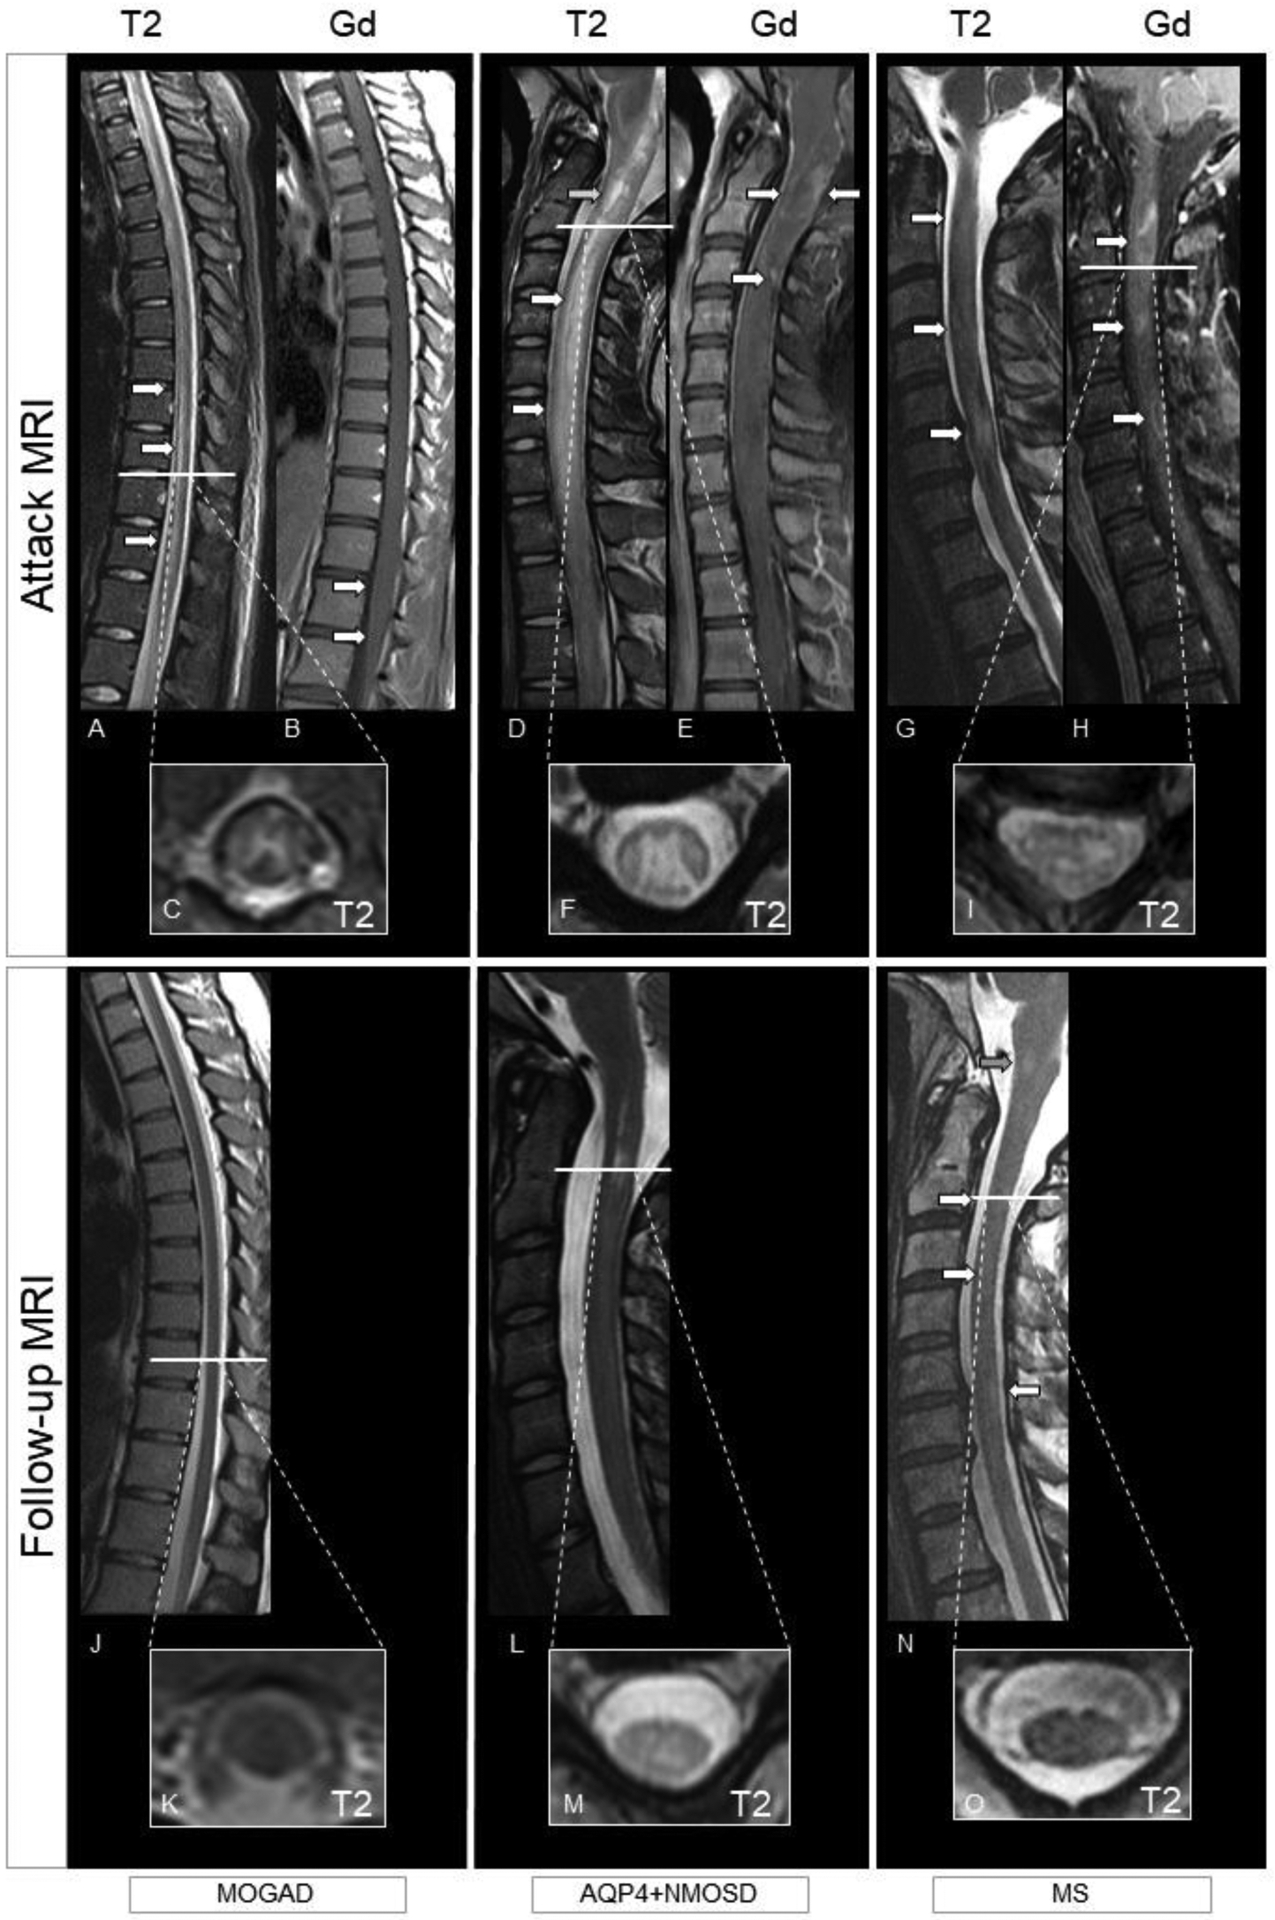

Figure 4. MRI examples of myelitis in patients with MOGAD, AQP4+NMOSD, and MS.

Top row shows MRI findings during the acute phase (T2-weighted images and post-contrast T1-weighted images), while follow-up up imaging is displayed in the bottom row (T2-weighted images). MOGAD: Longitudinally extensive myelitis (i.e., T2-lesion extending over at least three continuous vertebral segments) with a linear appearance involving the thoracic cord down to the conus (A, arrows, sagittal view). There is associated H-sign (i.e., exclusive involvement of the grey matter; C, axial view). Enhancement is absent, except for a mild leptomeningeal enhancement of the conus (B, arrows, sagittal view). The T2-lesion completely resolved on T2-weighted images at follow-up (J, sagittal view and K, axial view), with no evident atrophy. AQP4+NMOSD: Longitudinally extensive myelitis with a T2-lesion starting from the area postrema and involving the cervical cord (D, arrows, sagittal view) with associated swelling. Intralesional increased focal T2-hyperintensity similar to the CSF (i.e., brighter spotty lesion) is also present (D, green arrow). The T2-lesion is centrally located in both the grey and the white matter (F). Enhancement is inhomogeneous (E, arrows, sagittal view). At follow-up, the T2-lesion reduced in size on T2-weighted images (L, sagittal and M axial view) although still present. Residual atrophy of the cord is particularly evident on axial view (M). MS: Multiple focal short spinal cord T2-lesions (G, arrows, sagittal view) located in the peripheral white matter (I, axial view). All lesions enhance, with the bottom lesion showing a ring-pattern of enhancement (H, arrows, sagittal view). T2-lesions reduce in size and prominence of T2-hyperintensity persist on follow-up T2-weighted images (N, arrows, sagittal view and O, axial view). The patient also developed an interval T2-lesion (N, green arrow).

Abbreviations: AQP4+NMOSD=aquaporin-4-IgG positive neuromyelitis optica spectrum disorder; Gd=post-contrast T1-weighted images; MOGAD=myelin oligodendrocyte glycoprotein antibody-associated disease; MS=multiple sclerosis; T2=T2-weighted images.